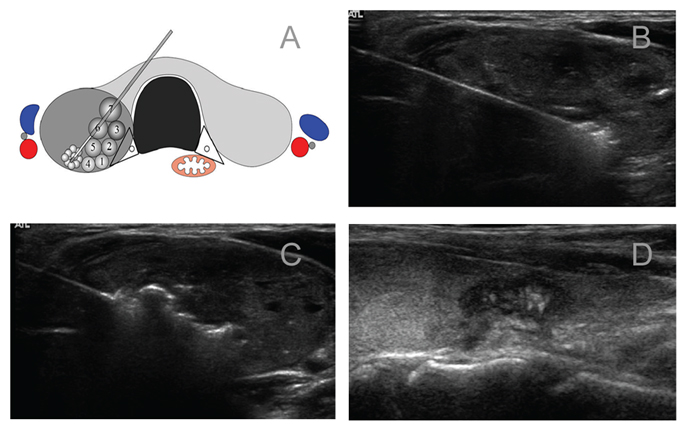

1.影像检查:超声或超声造影等,以详细了解甲状腺结节的位置、形态、大小、结节内部及周边血供情况及结节与周边结构的关系,确定最佳进针部位和途径。

3.将消融针在超声引导下逐渐穿入目标位置(一般多从结节的远处开始消融)